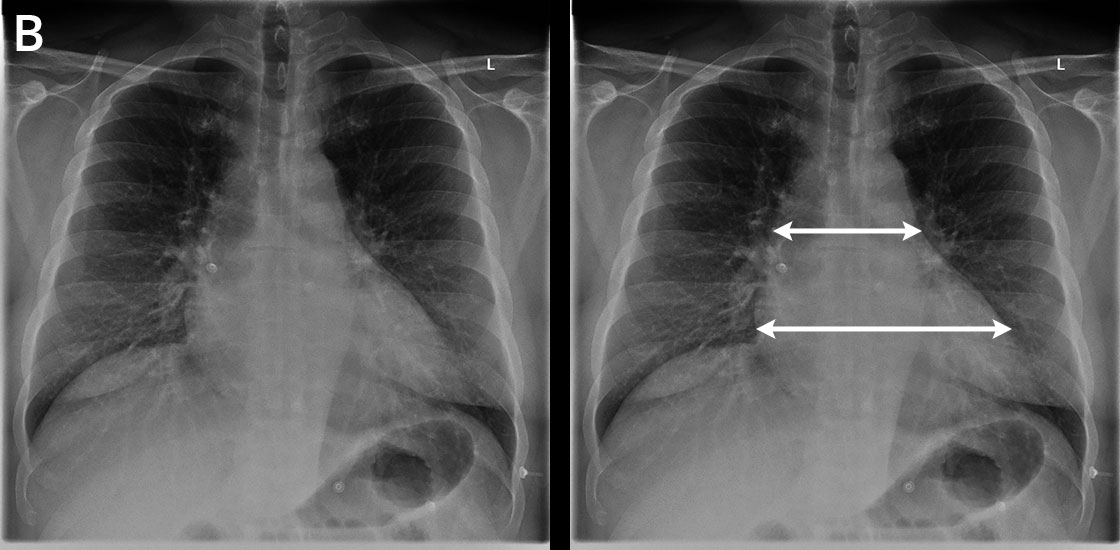

B. Kuusi vuotta myöhemmin mies on tutkimuksissa ohimenevien hemipareesioireiden ja veriyskösten vuoksi. Anamneesista ilmeni lepo- ja rasitushengenahdistusta, limaista yskää, sydämentykytystä ja rasituksensiedon heikkenemistä. Statuksessa lievä ylipaino, auskultoiden hienojakoista rahinaa oikealta, lievää leukosytoosia, CRP matala. Ei turvotuksia. Neurologinen status todettiin normaaliksi. Pään tt-kuvan lisäksi otetussa thoraxkuvassa löydökset olivat muutoin normaalit, mutta sydän on huomattavasti laajentunut. Keuhkoverekkyys oli vielä normaalirajoissa, eikä pleuranestettäkään ilmennyt. Jatkotutkimuksissa todettiin suuren sydämen syyksi dilatoiva kardiomyopatia. Pelkän thoraxkuvan perusteella ei siis voi arvioida, mitä sydämen suurentumisen taustalla on.